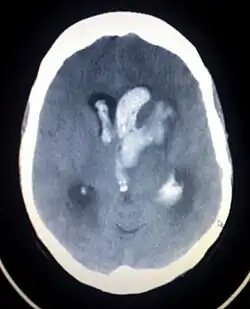

Intrazerebrale Blutung

CT-Aufnahme einer intrazerebralen Blutung (helle, zentrale Bezirke)